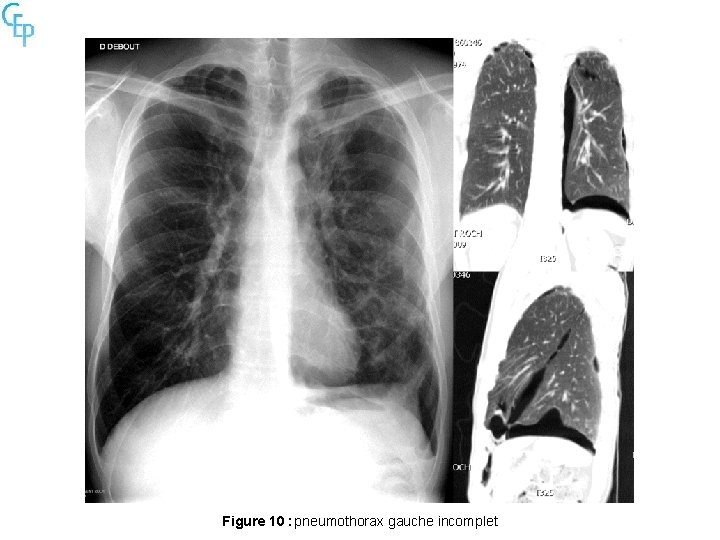

Figure 10 : pneumothorax gauche incomplet